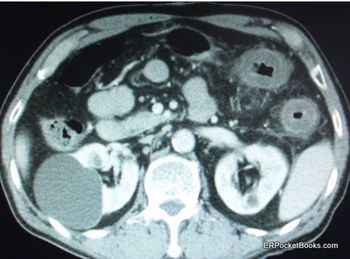

The patient has had 10 episodes of bleeding in the past 24 hours. Can you find clues to the underlying problem in the history and on the CT scan?